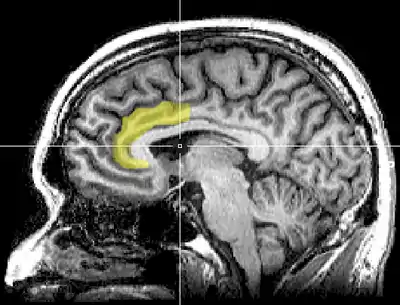

Cognitive dissonance produces a state of negative affect, which motivates the person to reconsider the causative behavior in order to resolve the psychological inconsistency that caused the mental stress.[100][101][102][103][104][105] As the affected person works towards a behavioral commitment, the motivational process then is activated in the left frontal cortex of the brain.[100][101][102][106][104]

The study Neural Activity Predicts Attitude Change in Cognitive Dissonance[108] (Van Veen, Krug, etc., 2009) identified the neural bases of cognitive dissonance with functional magnetic resonance imaging (fMRI); the neural scans of the participants replicated the basic findings of the induced-compliance paradigm. When in the fMRI scanner, some of the study participants argued that the uncomfortable, mechanical environment of the MRI machine nevertheless was a pleasant experience for them; some participants, from an experimental group, said they enjoyed the mechanical environment of the fMRI scanner more than did the control-group participants (paid actors) who argued about the uncomfortable experimental environment.[108]

The results of the neural scan experiment support the original theory of Cognitive Dissonance proposed by Festinger in 1957; and also support the psychological conflict theory, whereby the anterior cingulate functions, in counter-attitudinal response, to activate the dorsal anterior cingulate cortex and the anterior insular cortex; the degree of activation of said regions of the brain is predicted by the degree of change in the psychological attitude of the person.[108]

The biomechanics of cognitive dissonance: MRI evidence indicates that the greater the psychological conflict signalled by the anterior cingulate cortex, the greater the magnitude of the cognitive dissonance experienced by the person.

As an application of the free-choice paradigm, the study How Choice Reveals and Shapes Expected Hedonic Outcome (2009) indicates that after making a choice, neural activity in the striatum changes to reflect the person's new evaluation of the choice-object; neural activity increased if the object was chosen, neural activity decreased if the object was rejected.[109] Moreover, studies such as The Neural Basis of Rationalization: Cognitive Dissonance Reduction During Decision-making (2010)[35] and How Choice Modifies Preference: Neural Correlates of Choice Justification (2011) confirm the neural bases of the psychology of cognitive dissonance.[96][110]

The Neural Basis of Rationalization: Cognitive Dissonance Reduction During Decision-making[35] (Jarcho, Berkman, Lieberman, 2010) applied the free-choice paradigm to fMRI examination of the brain's decision-making process whilst the study participant actively tried to reduce cognitive dissonance. The results indicated that the active reduction of psychological dissonance increased neural activity in the right-inferior frontal gyrus, in the medial fronto-parietal region, and in the ventral striatum, and that neural activity decreased in the anterior insula.[35] That the neural activities of rationalization occur in seconds, without conscious deliberation on the part of the person; and that the brain engages in emotional responses whilst effecting decisions.[35]